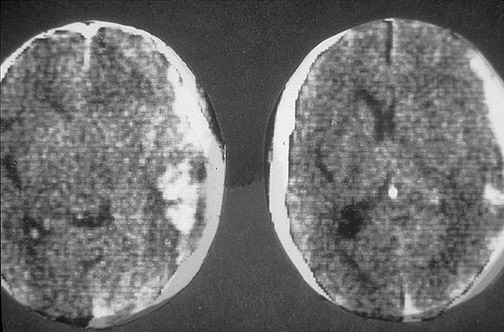

Image 4.1

This is the CT scan.